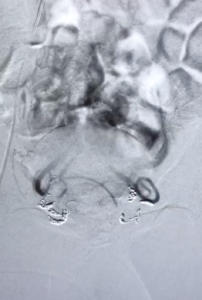

Contrôle artères rectales supérieures après embolisation

2. Il cathétérise l'artère mésentérique inférieure, puis les artères rectales supérieures qui sont alors occluses à l'aide de micro coïls (petits fils de platine souvent fibrés).

3. Il ferme la voie d'abord à l'aide d'un système de fermeture mécanique.